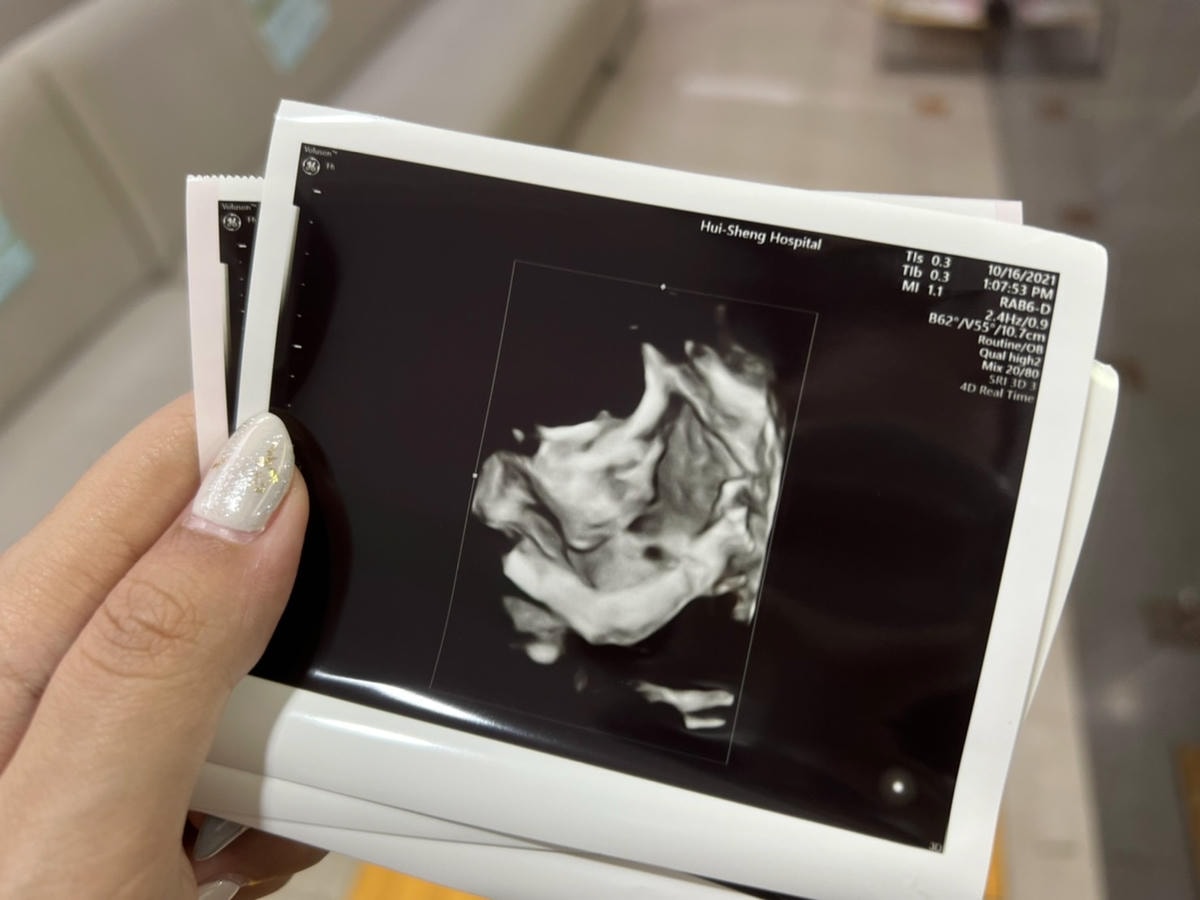

檢查完畢後,護理師告訴我可以下載 APP觀看超音波照片&影片,產檢完後,會很快的上傳到雲端,就可以自己下載存檔囉!

( 護理師跟我說完後我手刀下載APP,把超音波的影片下載,傳送給想看孫子的阿婆看 ![]()

也有拿到寶寶的超音波照片,照的好清楚喔 比我自己看的婦產科還清楚超多

最近產檢完全不知道照片在拍什麼… 謝謝蕙生醫院讓我看到超清楚的寶寶照可以留念